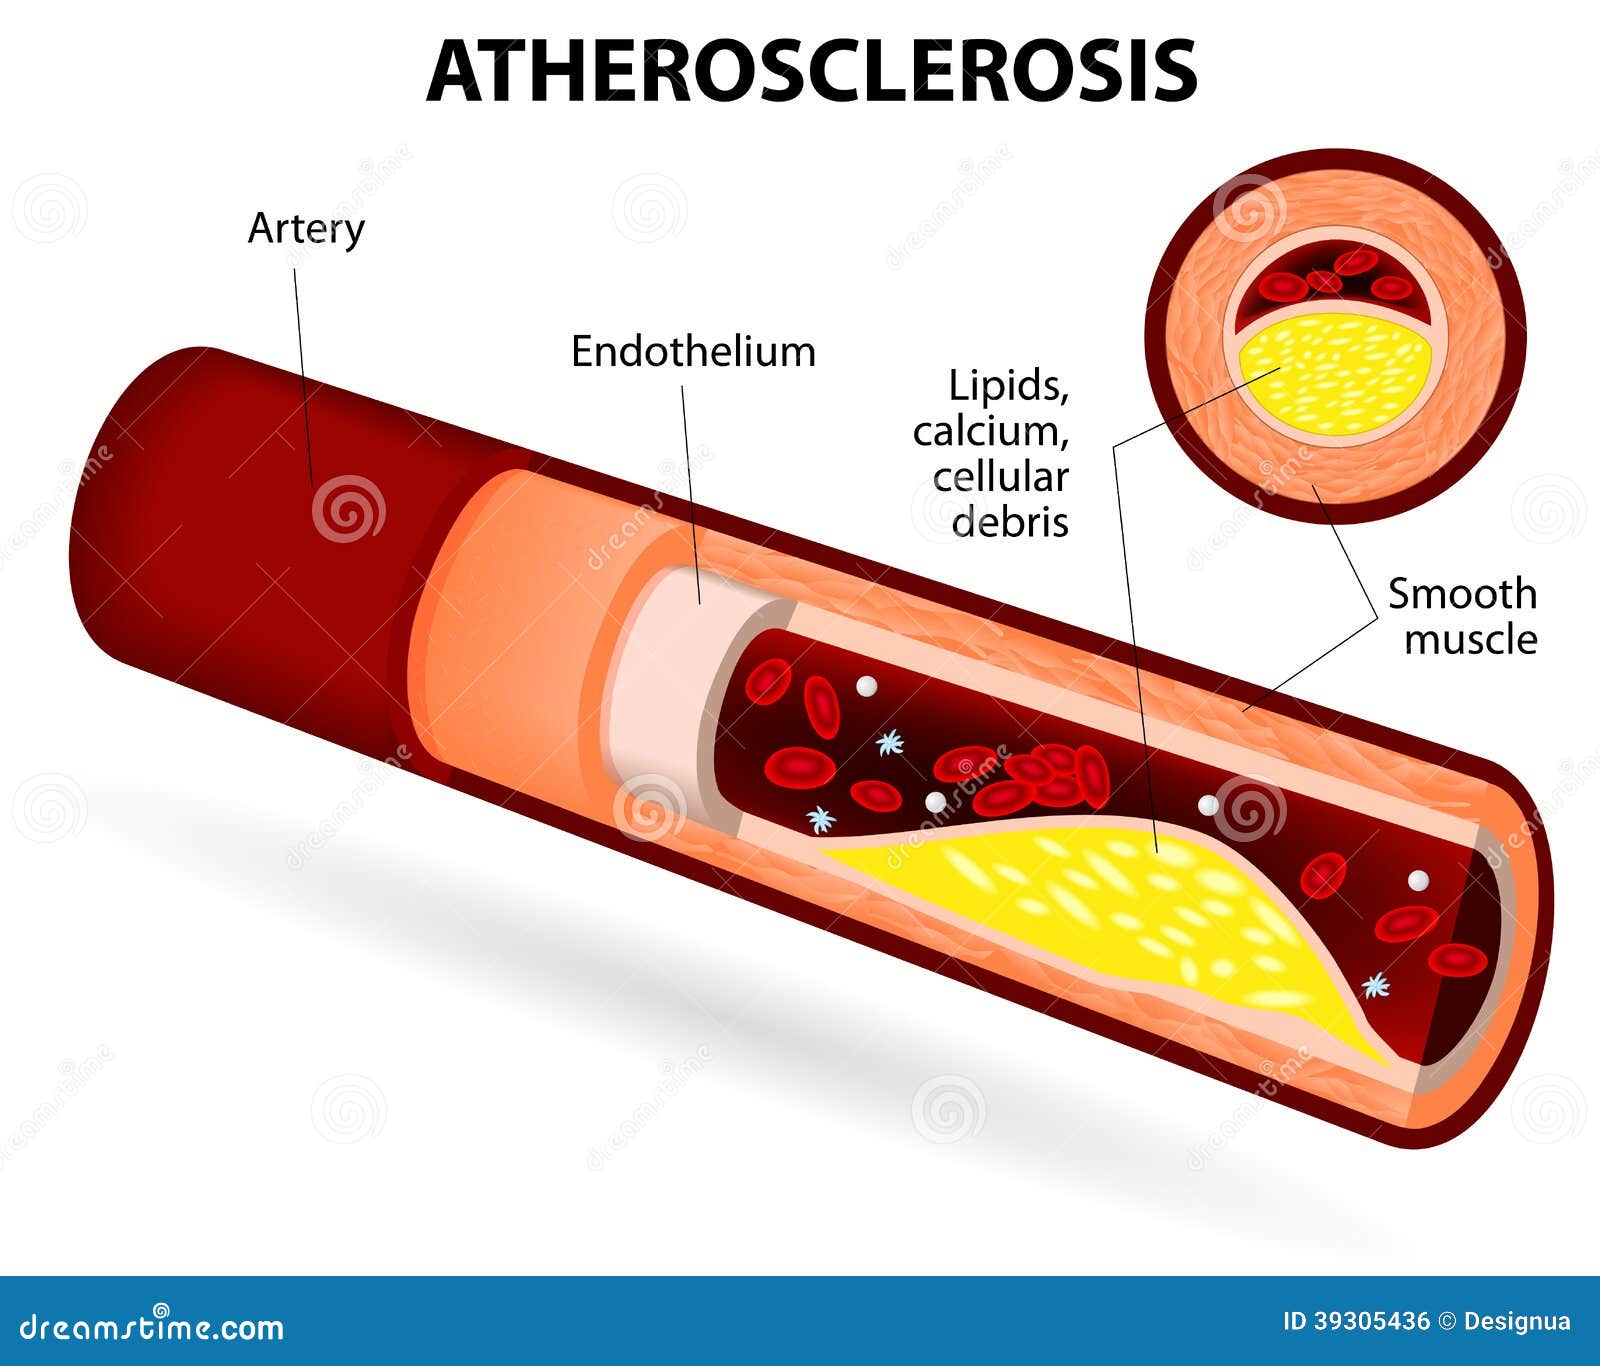

Atherosclerosis stock vector. Illustration of cardiovascular – 39305436

Atherosclerosis. Cholesterol plaques. Disturbance of lipid and protein …

Atherosclerosis, also known as “hardening of the arteries,” is a …